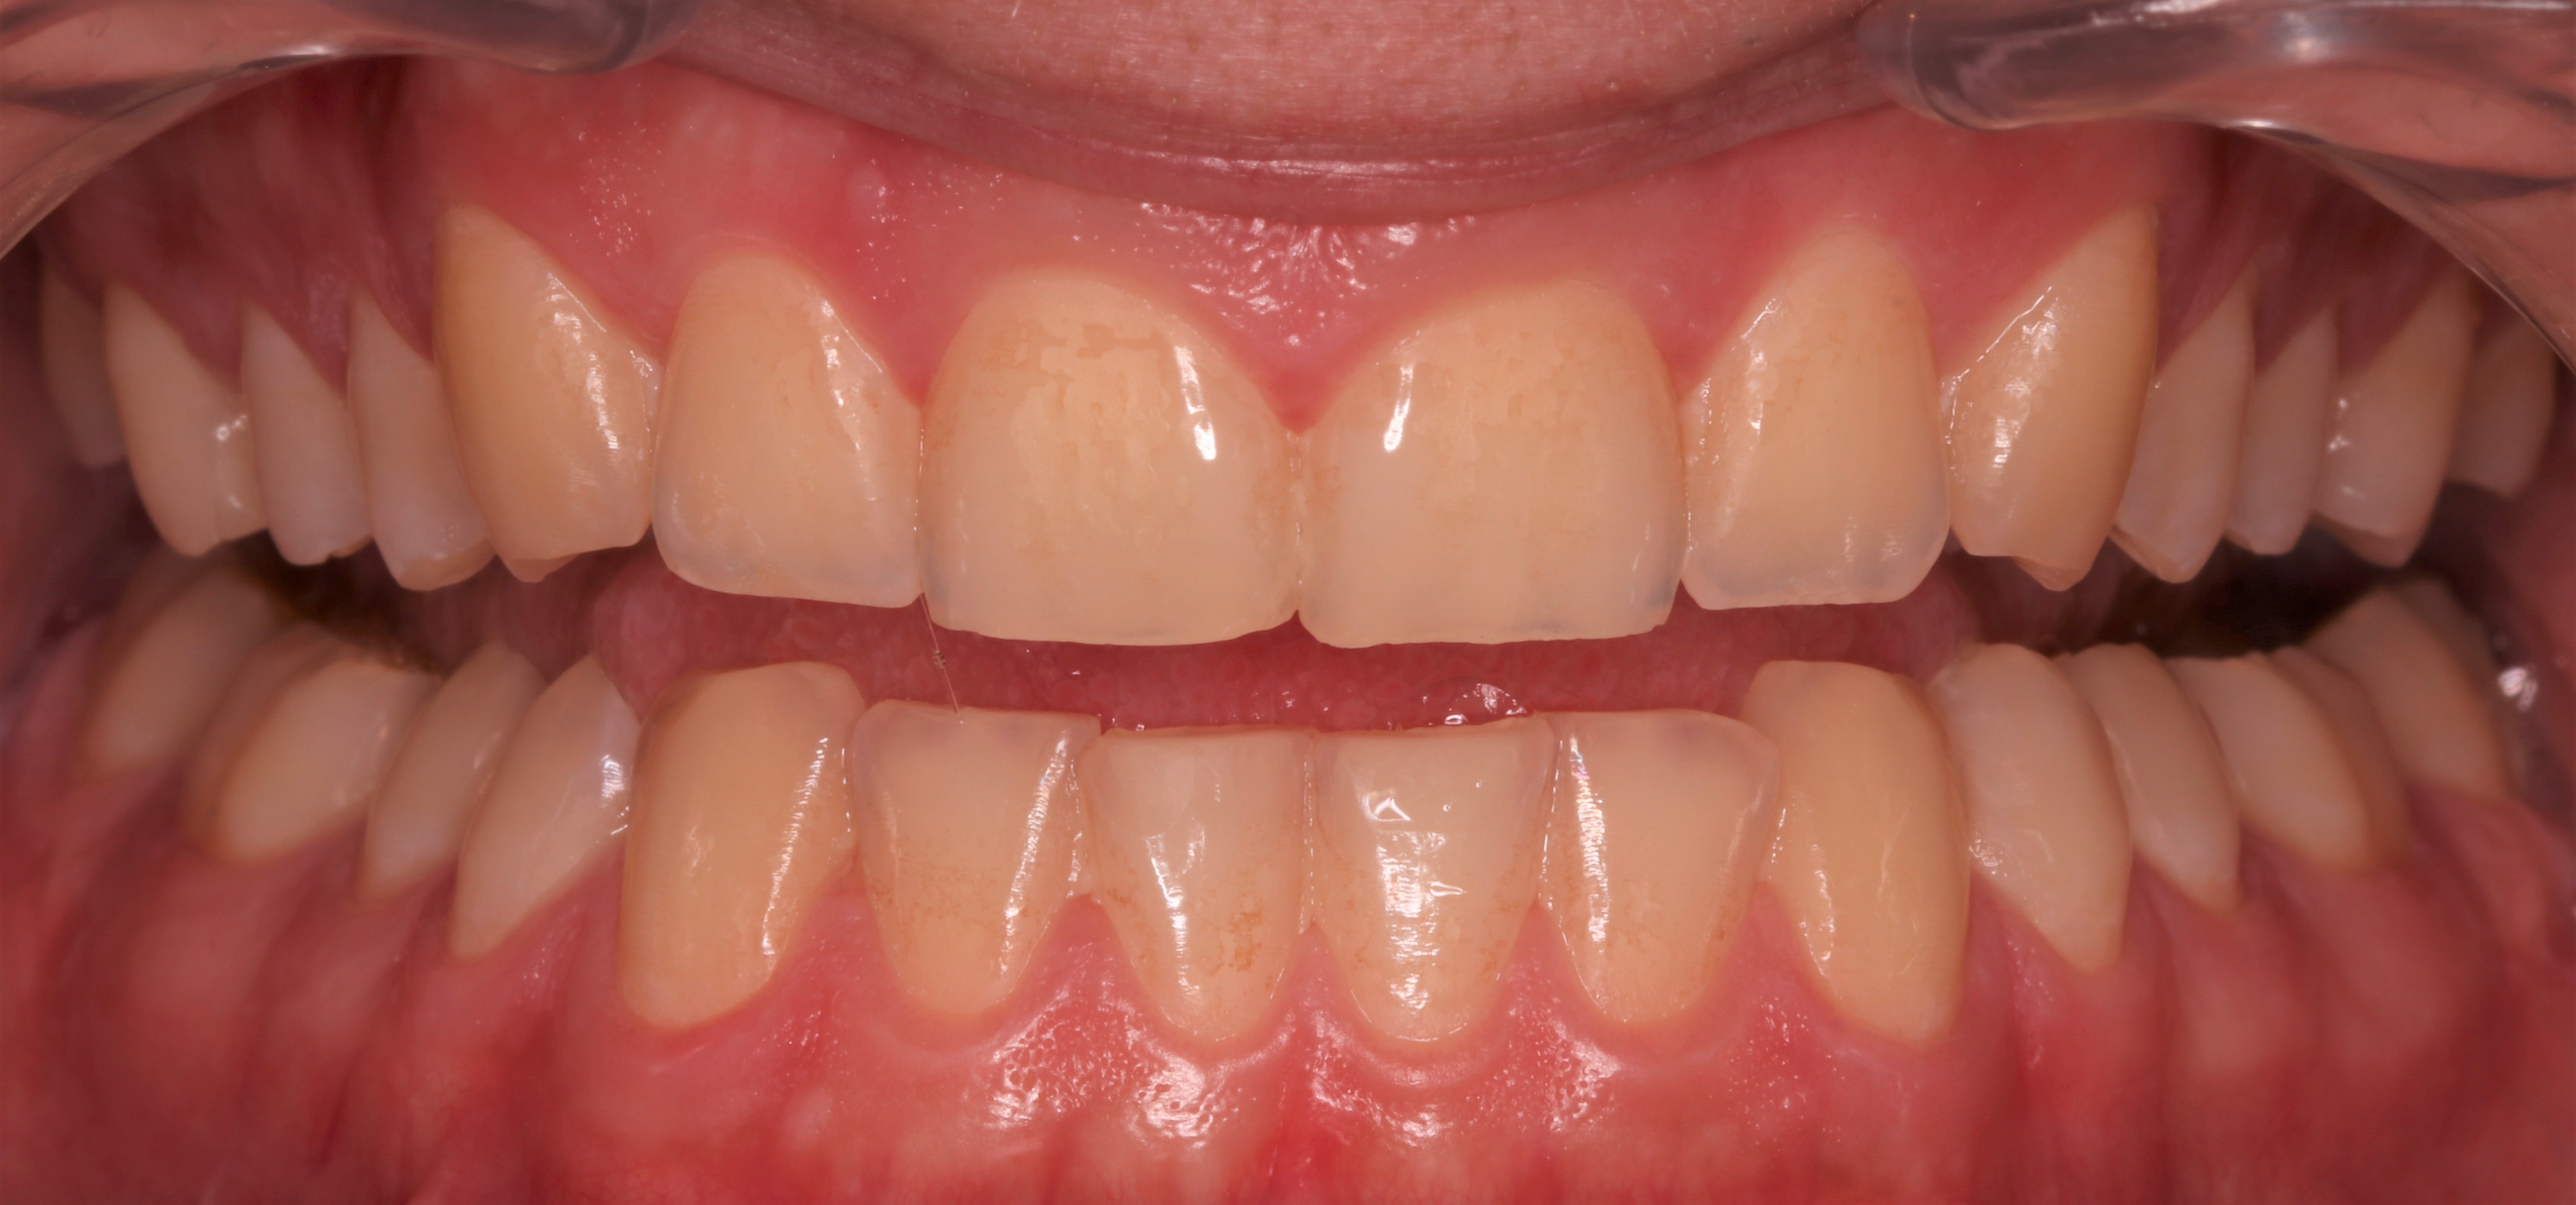

Pacjent, 18 lat, został skierowany w celu leczenia zachowawczego przed planowanym leczeniem ortodontycznym i odbudową startych zębów. W badaniu klinicznym stwierdzono niedostateczną higienę jamy ustnej – osad i złogi miękkie w przestrzeniach międzyzębowych, uogólnioną erozję szkliwa, starcie oraz liczne ogniska próchnicy pierwotnej zlokalizowane na powierzchniach stycznych zębów bocznych (ryc. 1‑4).

Ryc. 2. Sytuacja początkowa – zęby w rozwarciu.